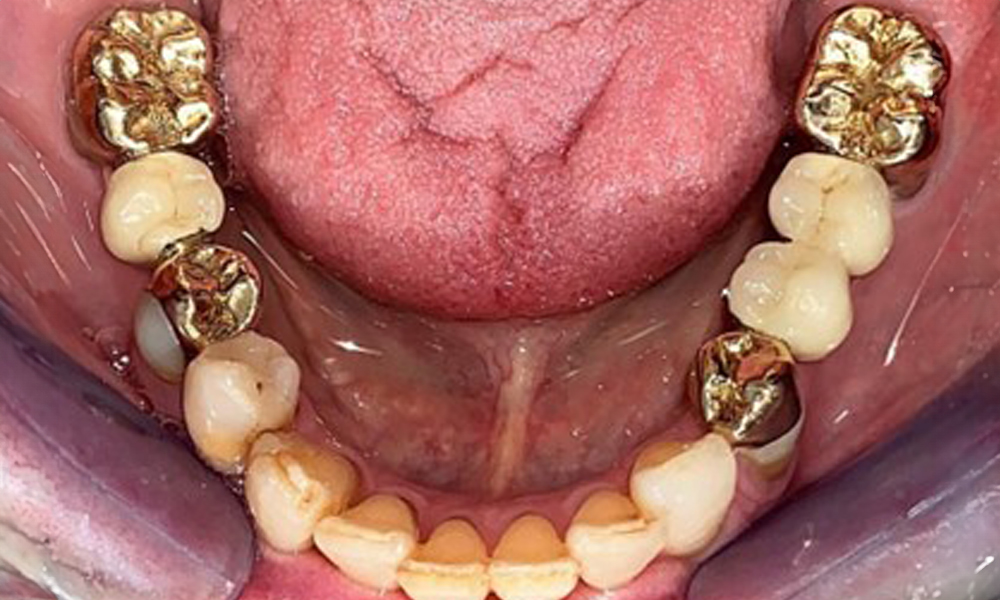

The patient was fitted with a combined removable maxillary telescopic prosthesis more than 25 years ago (Fig. 1, Fig. 2, Fig. 3) and is very happy with her dentures. The patient has an adequate fixed denture for the mandible (Fig. 4).

The dental findings are as follows: Combined removable implant and tooth-supported telescopic prostheses on implants 15, 13, 21, 23, 24, 25 and tooth 11 (Fig. 1, Fig. 2, Fig. 3). The patient was fitted with a fixed mandibular denture. Adequate bridges were present over 37 to 34 and 45 to 47 (Fig. 4), the crown margins were intact and there were no active caries. A composite filling with a marginal gap was present on tooth 43. There was mandibular gingival recession, exposing 1 to 3 mm of root surface. This also applies to 11.

Occlusal view of the mandible.

Fig. 4: Occlusal view of the mandible.